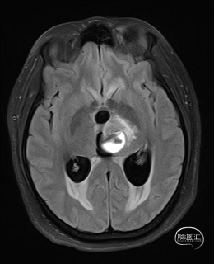

术前MRI检查

术前MRI检查提示左侧丘脑中脑海绵状血管瘤并卒中,梗阻性脑积水;

诊断:1.左侧丘脑中脑海绵状血管瘤并卒中,2.梗阻性脑积水;

年轻患者,较短时间内发生左侧丘脑二次出血,出现右侧面部及上肢麻木,复视,第二次出血后并发梗阻性脑积水,出现头痛。结合病史、神经系统体征、头颅CT及MRI检查,诊断左侧丘脑及中脑CM并卒中、脑积水明确,并导致了神经功能障碍,具备手术指征。

本例患者磁共振检查清晰显示病变位于左侧丘脑中脑区域,且位于丘脑内下方向中脑顶盖延续,病变的上部、前部、外侧部都有重要的神经组织,因此,手术从上方、前方、外侧方向切除病变均难以实施;